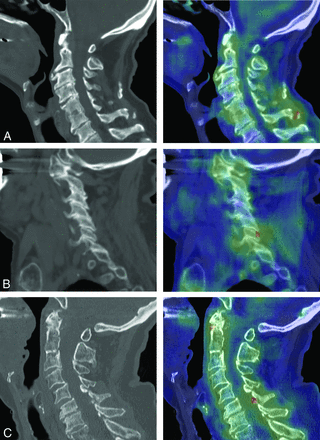

Because the number of false-positive flagged studies exceeded the number of true-positives (106 versus 67), we next sought to understand the poor positive predictive value of Aidoc by exploring possible failure modes of the false-positive studies. Each study flagged by Aidoc is accompanied by a probability heat map highlighting the suspected fracture identified by Aidoc, thus allowing us to identify the etiology of each false-positive finding (Table 2). The most common etiology was the presence of degenerative structures such as a degenerative ossicle (Fig 2A), facet degeneration (Fig 2B), ossification of the ligamentum flavum (Fig 2C), or other degenerative cortical irregularities. The next most common sources of false-positive findings were pathologies outside the cervical spine and scope of the algorithm, such as rib or skull fractures (Fig 3A), and nonpathologic anatomic variants (Fig 2B, -C). False-positives were also found to have been triggered by motion artifacts or normal anatomy, and in a small number of cases, we were unable to identify any abnormality.

Examples of degenerative findings falsely flagged by Aidoc. Each panel shows the sagittal noncontrast cervical spine CT (left) and the Aidoc key image indicating the flagged pathology in red (right). A, A chronic ossicle falsely flagged by Aidoc. B, False-positive findings triggered by facet degeneration. C, Ossification of the ligamentum flavum incorrectly identified as a fracture by Aidoc.